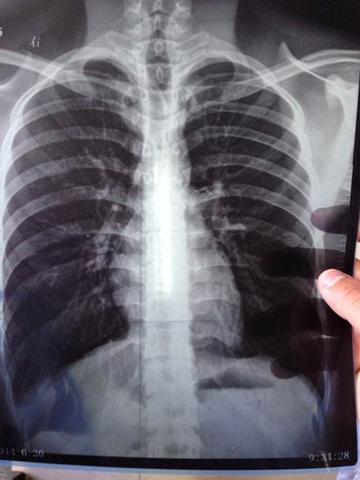

根據《三立新聞》報導,知名男星顏正國於7日因肺腺癌不幸辭世,享年僅50歲,突如其來的死訊震撼演藝圈!他於近期確診第四期肺腺癌,9月底住進醫院接受治療,但病情急速惡化,短短數週後便離世。

北市聯醫陽明院區胸腔內科專家表示,肺腺癌被稱為「沉默殺手」,因為在疾病初期幾乎完全沒有明顯徵兆,容易被誤認為「感冒」而錯過最佳治療時機。等到出現症狀時,8成以上的病例都已經進展到末期階段。有病患的腫瘤甚至長到10公分大小,仍未察覺任何不適,直到病情急遽惡化才被送進加護病房。

彰化秀傳醫院指出,肺腺癌的病程發展可分為三個階段。初期症狀包含持續性咳嗽,偶爾會有血痰,胸部會感到疼痛,這是因為腫瘤壓迫到胸腔結構或刺激到神經。此外,運動時會特別容易喘。

到了中期,患者的咳嗽症狀會更加頻繁且嚴重,血痰情況增加,胸痛感加劇且持續時間更長,尤其在深呼吸或咳嗽時特別明顯。就連一般日常活動都會感到呼吸困難,喉嚨也可能因腫瘤壓迫而疼痛發炎。

末期時,病患除了會有更嚴重的持續性咳嗽和大量血痰外,胸痛會變得持續且劇烈。即使躺著休息也會感到嚴重呼吸困難,同時會出現明顯的體重下降,全身持續感到疲倦虛弱,這些都是腫瘤影響到患者的進食和全身健康狀況的警訊。